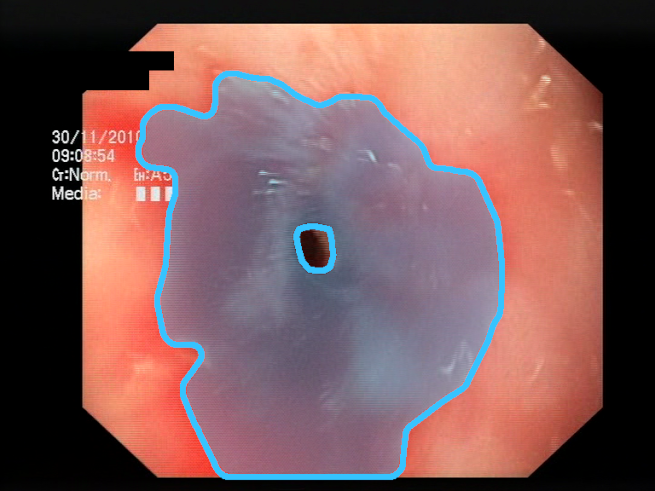

As a result of the design process, nine high-level features (denoted F1–F9) were defined. The features are proposed with simple definitions that also include exemplary images, presented in Table 1. For each image, a blue annotation is presented, illustrating the image regions where the feature is hypothetically present.

Table 1.

Definitions of the nine proposed visual features of endoscopic bleeding. For each image, a blue annotation is presented, which illustrates the area of the image where the feature is hypothetically present.